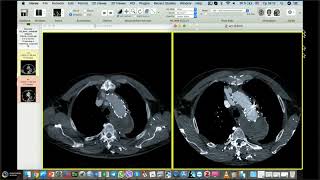

Информативные вебинары по радиологии для Рентгенолаборантов.